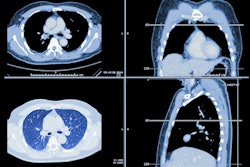

The group identified 7,720 patients who underwent baseline low-dose CT (LDCT) exams between April 2021 and December 2022 as part of a lung cancer screening program. The team tracked sociodemographic information such as patients' sex, race, ethnic group, language, and zip code, as well as and clinical characteristics such as smoking status, Lung-RADS score, and the presence of any other interstitial lung diseases. Patients included were eligible for lung cancer screening under either the 2013 or the 2021 USPSTF guidelines (1,539 and 727 patients, respectively); mean age at screening under the 2013 guidance was 64 years and under the 2021 guidance, 57 years.

The investigators found that, under the 2021 recommendation, individuals who underwent lung cancer screening had lower percentages of Lung-RADS 3 and 4 scores compared with those screened under the 2013 recommendation (8% vs. 9.4% and 5.2% vs. 8%, respectively), as well as higher percentages of Lung-RADS 1 and 2 scores (12.5% vs. 11.1% and 74.3% vs. 71.3%, respectively).

"Our results suggest that the eligibility-criteria expansion of the new USPSTF lung cancer screening guidelines may promote earlier detection of smoking-related lung malignancies," the group concluded.